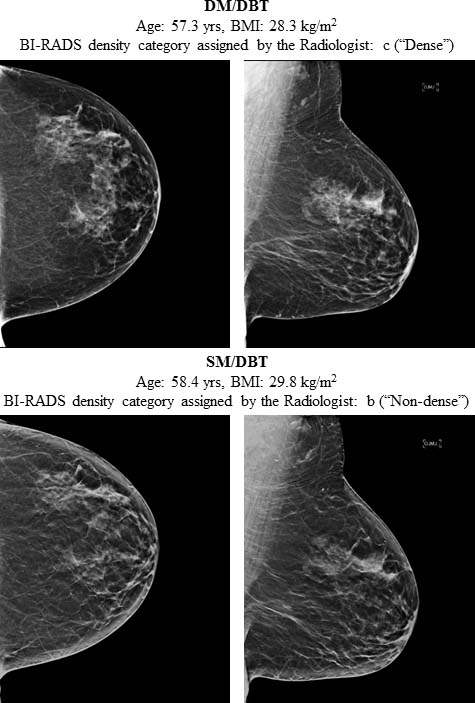

Although digital mammography (DM) has long been the foundation of breast cancer screening, new imaging modalities are increasingly being used, including digital breast tomosynthesis (DBT) and synthetic mammography (SM).

In 2011, the FDA approved the use of DBT in combination with DM imaging. In 2015, the FDA approved the use of synthesized 2D images, which are reconstructed from the DBT data set to replace DM imaging, lowering the dose of DBT imaging.

A statistical analysis of the study data showed breast density assignments varied greatly by the screening method used.

“We observed an overall trend of downgraded breast density when imaging was performed with either DM/DBT or SM/DBT compared with DM alone,” Dr. Gastounioti said. “These effects were more prominent among African-American women and women with higher BMI.”

Compared to standard DM imaging, the odds of a high-density assessment were reduced by 31 percent and 57 percent respectively when mammographic imaging was performed with DM/DBT or SM/DBT. The odds of receiving a high breast density assignment after SM replaced DM were reduced by 38 percent.

The density downgrade may be due to the perception of less fibroglandular tissue in the 3D display of DBT imaging compared to DM’s flat, 2D display, as well as differences in the appearance of the denser glandular tissue and the fatty tissue in the reconstructed SM imaging.